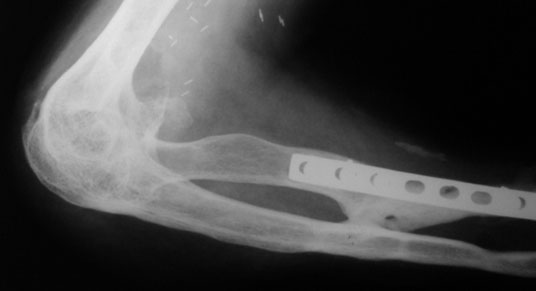

Xray before surgery

This 30 year gentleman had been through a lot. He had multiple fractures after a road traffic accident about 5 years ago. He fracture of the right femur, right tibia, both bones of right forearm with fracture of proximal humerus. All open fractures. When he came to us he had a near fused elbow – just a jog of movements.

The distal humerus has been shaped into a notch with the olecranon shaped into a hook creating two congruent surfaces and a flexion-extension axis.